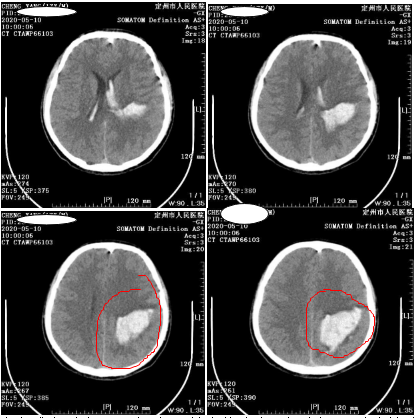

接诊医生为小雷急查头颅CT,并请神经外二科主任肖都盼会诊,肖主任查体发现小雷右侧肢体偏瘫,不仅精神差,还伴有嗜睡症状,肌力1级,头颅CT结果显示小雷左顶枕叶脑出血破入脑室系统,出血量约50ml。

开始,肖主任通过影像发现小雷左顶部动静脉畸形团约3

cm

×1.5cm大小,可见左侧大脑前动脉末端供血,及两根粗大引流静脉引流至上矢状窦。

出血位置顺利找到。

高密度影为胶水显影

术后,小雷神志清楚,语言流利,右下肢肌力1级,左侧肢体肌力5级,复查头颅CT显示血肿基本清除

。